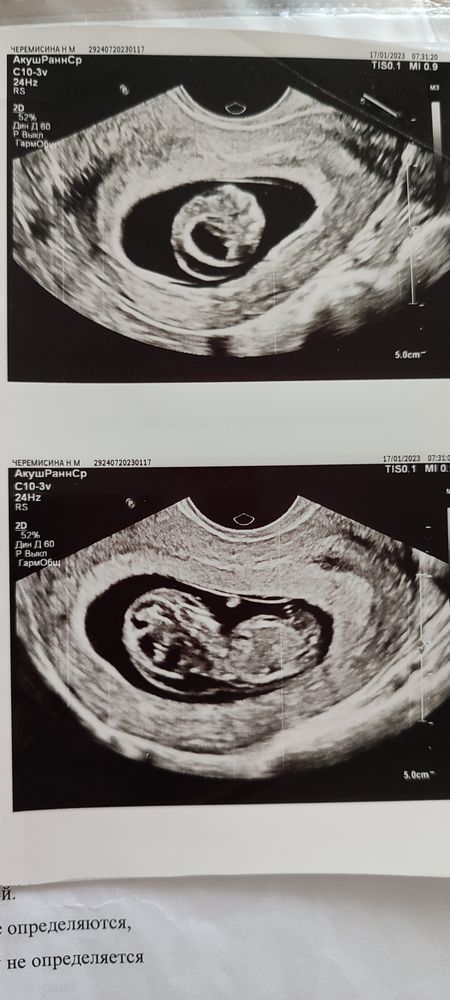

Девочки, я за поддержкой, плачу каждый день. В общем, мне 42 года, вторая беременность ЭКО, первая - все хорошо (мальчик, КС). На сроке 11н2д КТР 35 мм, что соответствует 10н3д. ТВП не измеряли, но по фото и так уже все видно. НИПТ жду результаты. Понимаю, что скорее всего будет прокол и, вероятнее всего, все плохо. Но очень хочется надеяться. Это был последний эмбрион. Еще на один круг не пойду - устала от этого.

Покидайте в комментарии ваши фото УЗИ при КТР около 35мм, если есть. Буду благодарна. Расскажите, было ли у кого такое - очень страшно. Следующее УЗИ у меня во вторник. Как же медленно время идет! За отклики всем большое спасибо.

Добрый день. У меня остались параметры примерно с этого срока.